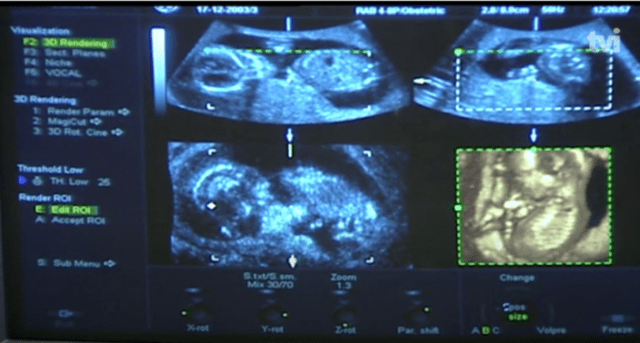

O caso de um bebê que nasceu sem olhos, nariz e parte do crânio, na